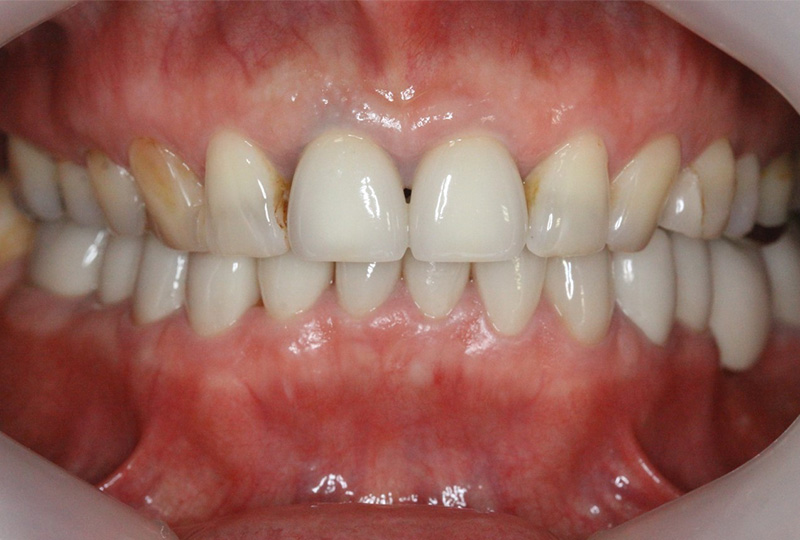

審美性にこだわった治療から保存が難しいと言われた歯の保存やお口全体をより良い状態にする一歩進んだ専門的な治療を行います。